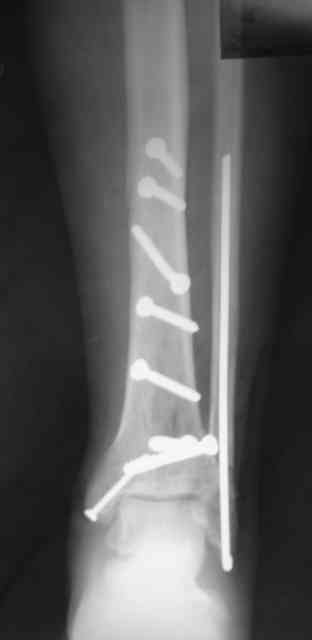

Сегодня прооперировали. Длительность 4-50. Начали как и говорил сверху вниз линейным разрезом - фиксация задне-латерального отломка к проксимальному 2мя винтами, затем "прилепили" к ним передне-медиальный (пришлось повозиться - была интерпозиция и довольно "сложный" винт) - к проксимальному 1 винтом и к задне-латеральному 1 винтом.Кстати на фото видно - у передне-медиального отломка еще осколок в области сустава, несколько смят. Далее началось веселье - второй доступ - задне-наружный к латеральной лодыжке и заднему краю, но оказалось, что задний край больше задне-медиальный (по снимкам было непонятно). Плюс к этому репозиция его мягко говоря сложновата (больной на спине, стол низкий и не поднимается). В общем выставили, фискировали 2мя винтами, на ЭОПе вроде стал, только верх отошел. Латеральную лодыжку заведующий решил интрамедуллярно (не хотел еще винты толкать), сначала 3мм спицей - нестабильно, затем 4мм стержень (не помню по автору) - ОК (кстати в месте перелома мелкая крошка - дефект до 5х7 мм по кортикалу). Ну медиальная лодыжка стандартно - третий разрез - винт 3,5 мм. Визуально все стабильно. На Р-контроле - видна небольшая ступенька заднего края по одному из контуров.

Рентгенограммы

Нельзя ли попросить снимки именно голеностопного сустава. Представлены снимки голени в нижней трети.Сустав фактичеси не виден.

Александр, если вы имеете в виду послеоперационные Р-граммы - то это все что есть. А сустав виден достаточно, чтобы оценить то что есть

Вы представили снимок голени в нижней трети. На сустав луч упал косо, это искажает.

Есть подозрение, что имеется ступенька заднего края, внутренняя лодыжка оттопырена. Взаимоотношения в суставе важнее, чем точная репзиция диафиза.

В боковой проекции - диастаз, 0,5-1мм.

P.S. Все-таки собирать оскольчатый перелом большеберцовой кости просто винтами - несколько неправильно...